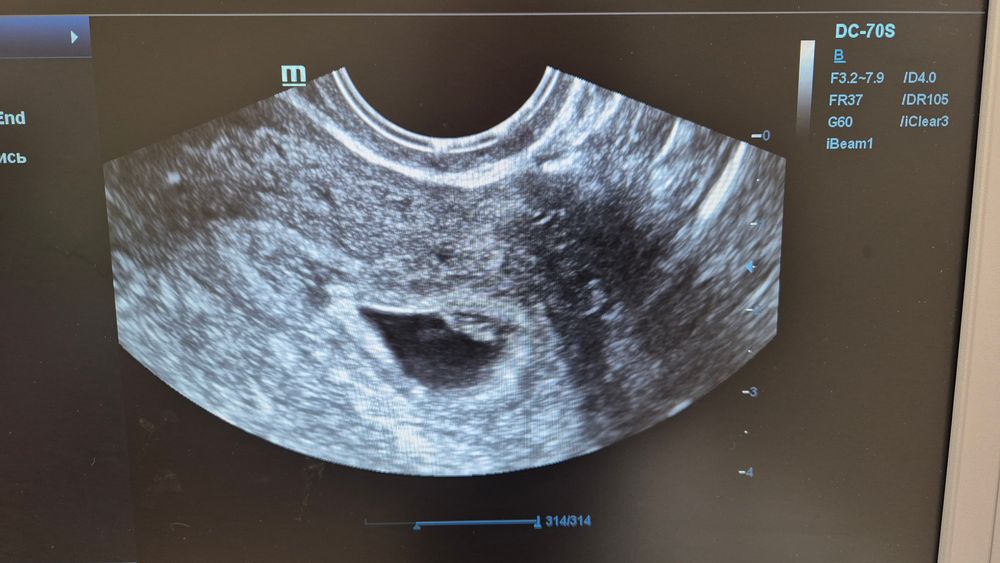

Сделали УЗИ, беременность маточная, эмбрион+сб .Это очень радует. Врач прописала L-тироксин, сказала в 12 недель пересдать, вроде не пугала, но как то боязно. + прописала ипрожин 100 на ночь.